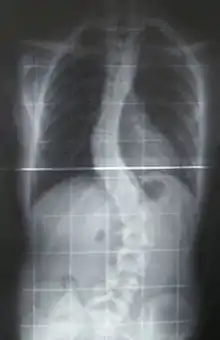

Skoliose (fra græsk σκολίοσις, skoliosis, skævhed) eller rygskævhed er en sygdom, hvor rygsøjlen er deform sådan, at den har en krumning til siden. Oftest vil ryggen have to krumninger, sådan at man på en patients ryg kan se, at rygsøjlen har form som et S. Sædvanligvis vil rygsøjlen også være roteret.

Patientens skoliose måles på røntgenbilleder samt på kroppens overflade, typisk hver 6. til 12. måned, og hvis den ikke progredierer og/eller er under behandlingsgrænsen startes ingen behandling.